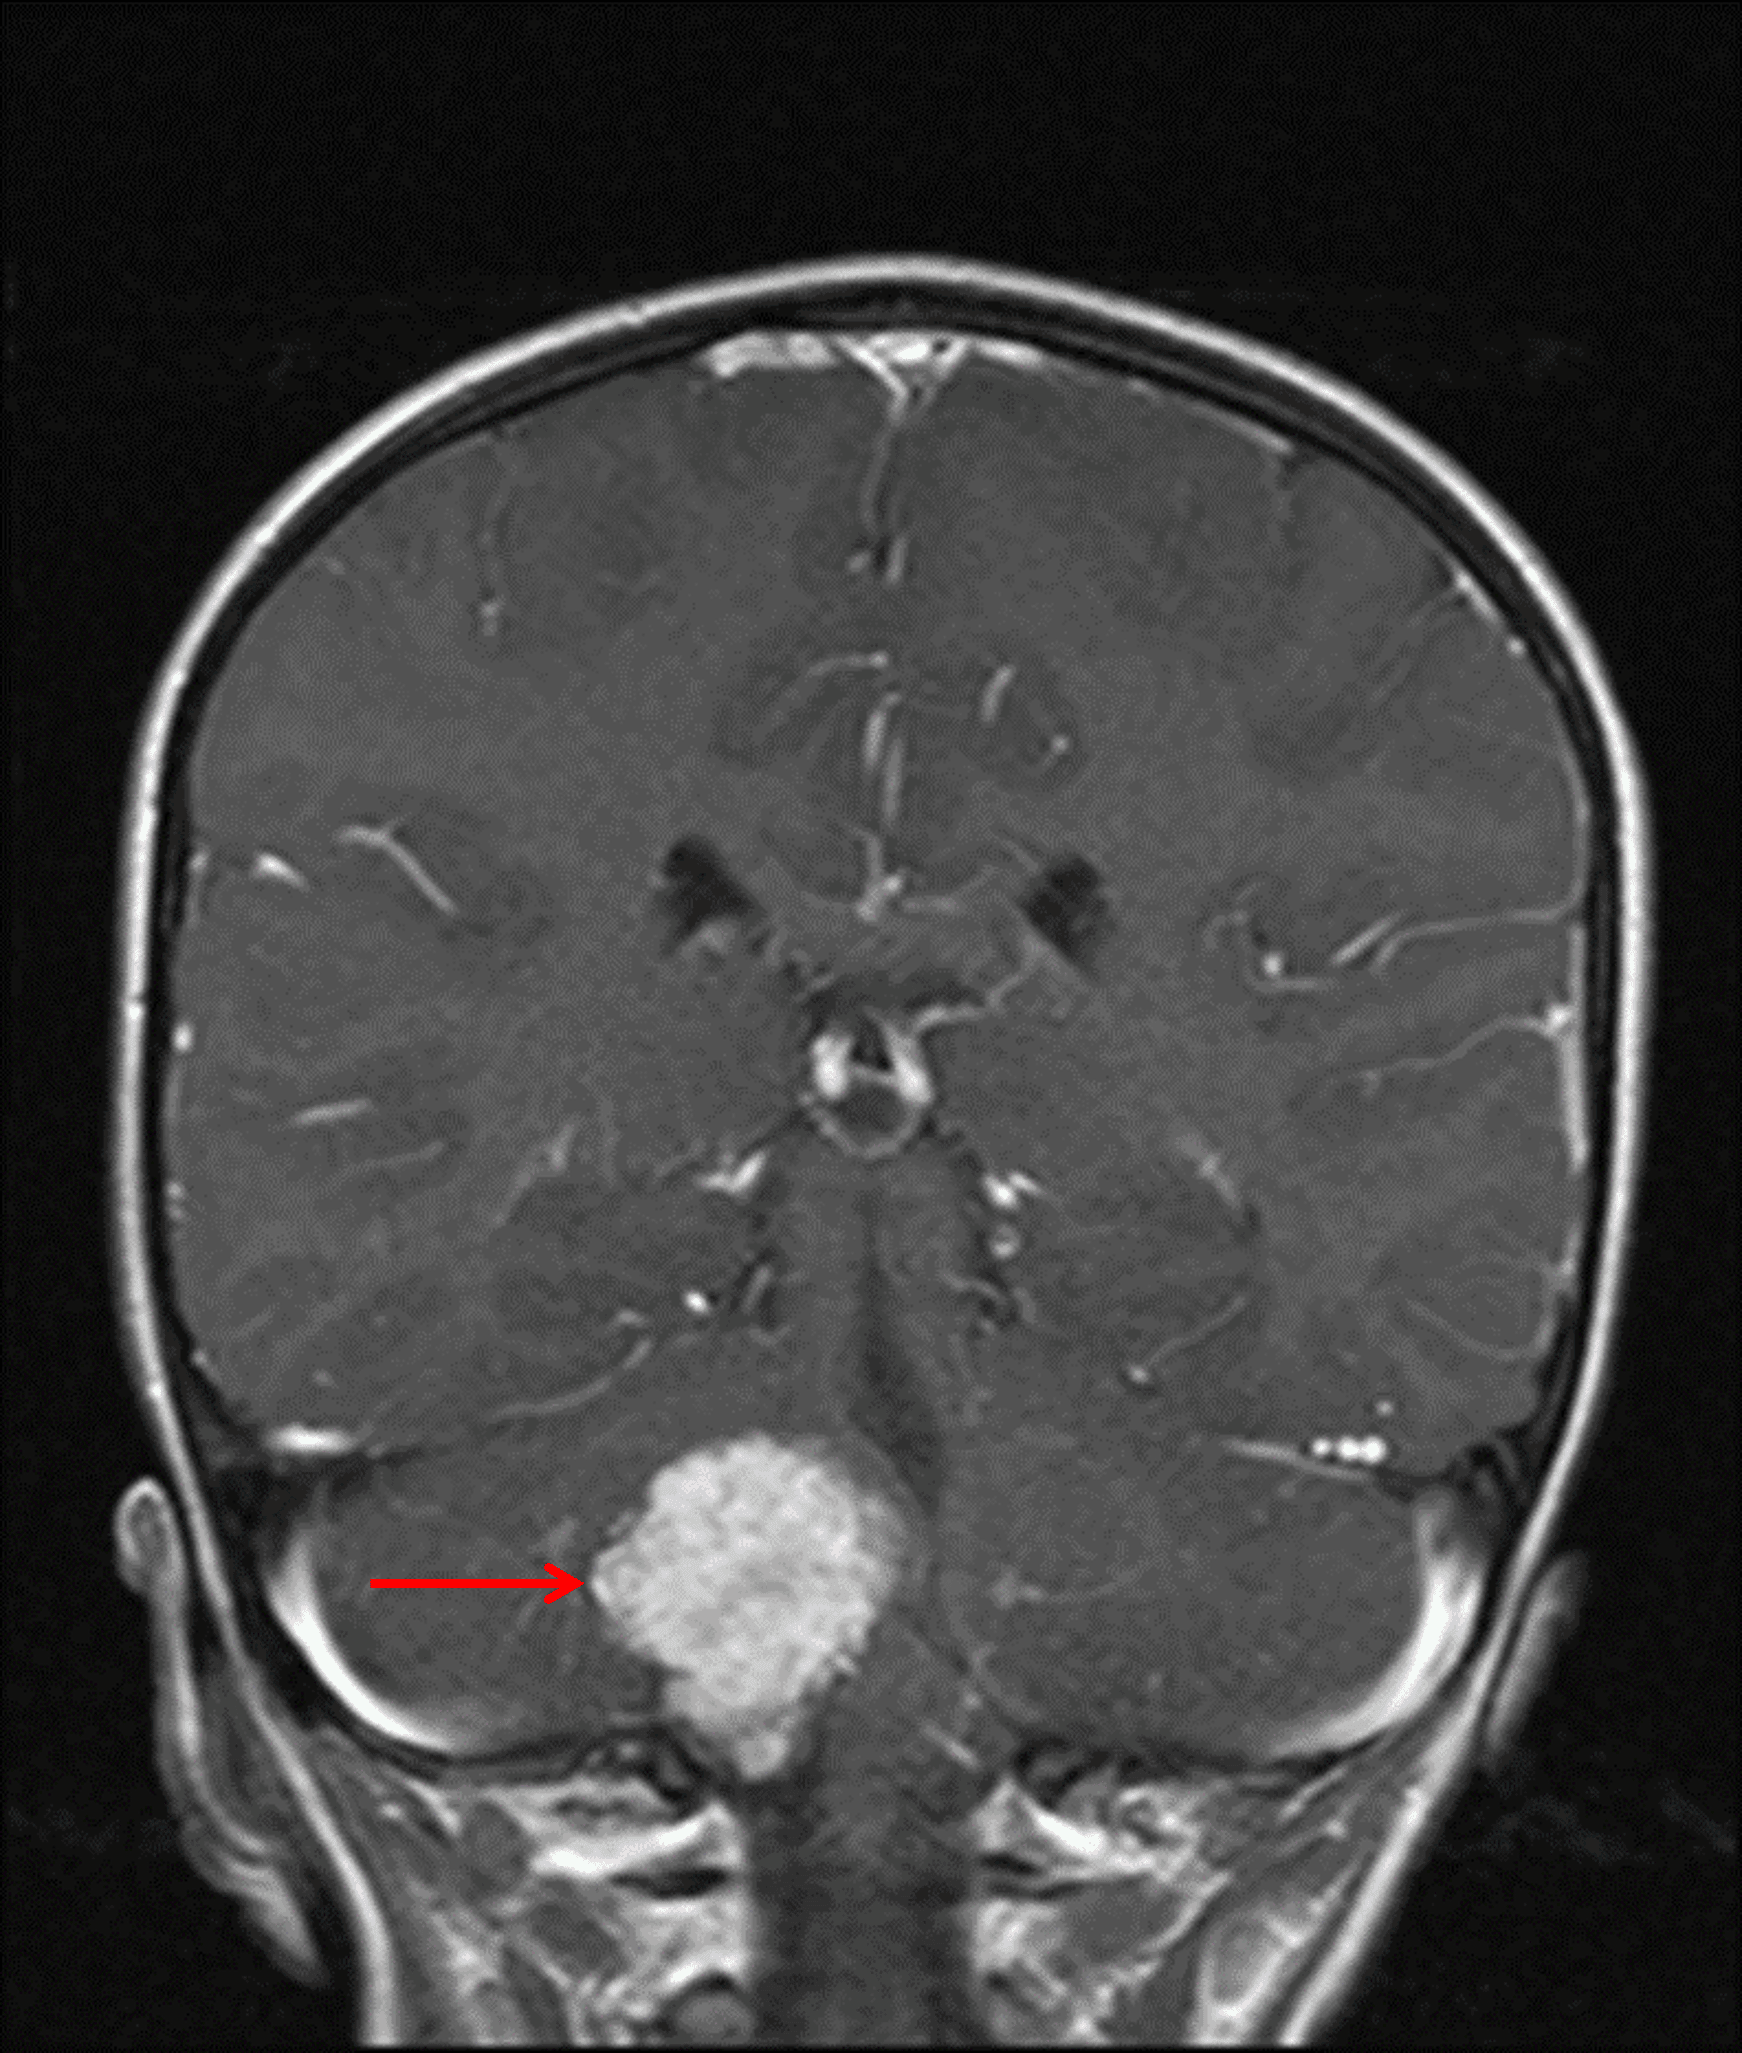

• Avidly enhancing extra-axial mass with frondlike projections measuring 3.5 x 3 x 3 cm centered in the right foramen of Luschka with superior extension into the fourth ventricle and inferior extension through the foramen magnum

Avidly enhancing mass centered in the right foramen of Luschka (red arrow), consistent with a choroid plexus tumor.

Choroid plexus papilloma